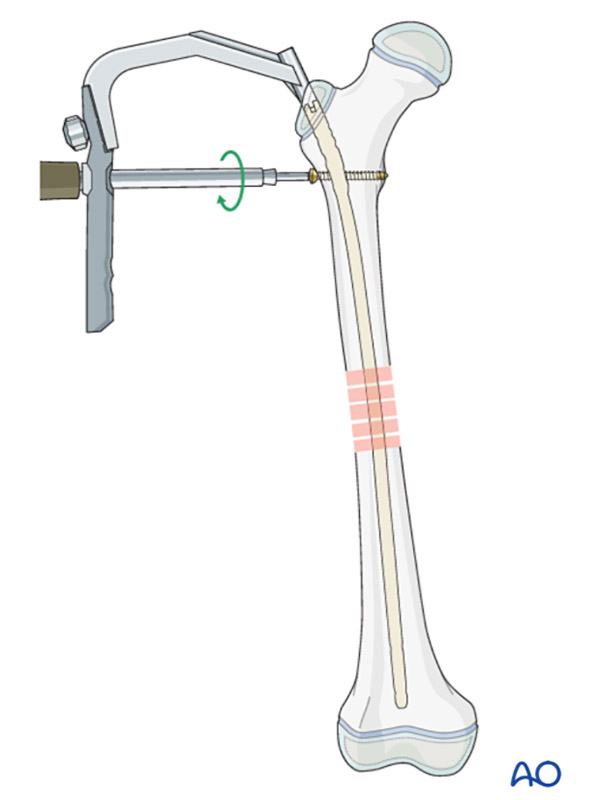

The new femoral shaft module comprises treatments depending on fracture type and patient age: casting, elastic stable intramedullary nailing, locked intramedullary nailing, external fixation, and plating.